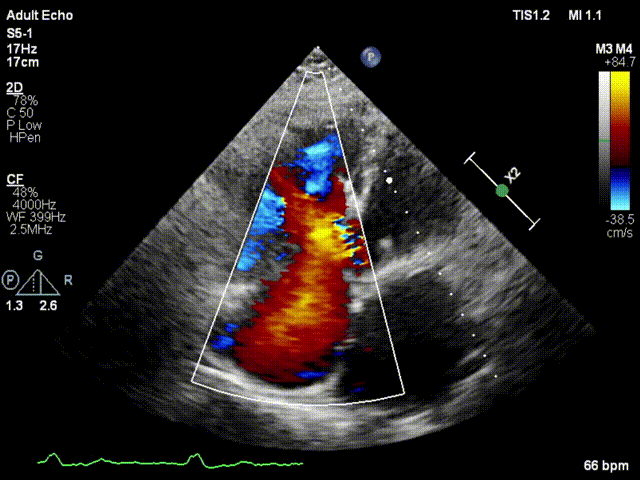

本次接受治療的患者是一名74歲的女性,14年前因風(fēng)濕性心臟病行二尖瓣生物瓣植入術(shù),合并房顫。近3年來反復(fù)因腹脹、納差、下肢水腫入院,藥物治療欠佳。心臟超聲顯示三尖瓣極重度反流(有效反流口面積:0.76cm²,反流容積:79ml),繼發(fā)性右房室增大及上、下腔靜脈增寬(右房上下徑*左右徑:52*41mm,右室左右徑:46mm,下腔靜脈:29mm),右室收縮功能正常,肺動脈收縮壓 43mmHg,左心室射血分?jǐn)?shù)73% 。患者既往開胸手術(shù)史,術(shù)前評估STS 評分為7.02分,CRS 9分,無法接受體外循環(huán)下三尖瓣外科手術(shù)。面對這一傳統(tǒng)治療無法解決的困境,葛均波院士及其團(tuán)隊(duì)周達(dá)新教授、潘文志教授、張?jiān)床┦俊㈥惿┦考靶某业呐舜湔浣淌凇⒗顐ソ淌诮?jīng)過討論決定,采用創(chuàng)新的Lux-Valve Plus系統(tǒng)為患者進(jìn)行經(jīng)血管三尖瓣置換。

手術(shù)在患者全麻狀態(tài)下進(jìn)行,采用經(jīng)右側(cè)頸靜脈作為入路,將裝載有人工瓣膜的輸送器緩慢推送至右心房;并在經(jīng)食道超聲和DSA的引導(dǎo)下小心調(diào)整輸送器角度,將輸送器送入右心室;逐步釋放瓣膜錨定裝置和盤片,調(diào)整瓣膜位置后,錨定瓣膜完成植入。術(shù)后右房壓明顯下降,從術(shù)前的25/10(16) mmHg降至術(shù)后即刻的12/7(10) mmHg,術(shù)后超聲提示人工三尖瓣同軸性良好,固定牢固,無反流及瓣周漏,手術(shù)室即刻拔除氣管插管。